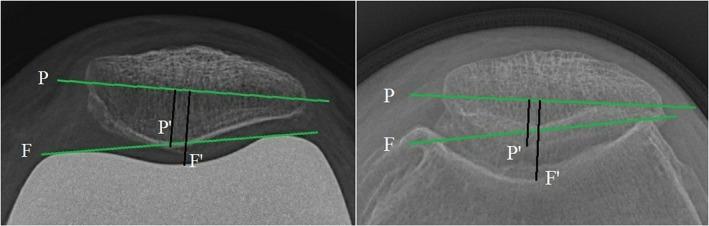

All consecutive patients who underwent unilateral total knee arthroplasty (TKA) with medial pivot prosthesis (Group MP, 126 cases) between September 2016 and April 2018 were enrolled in this retrospective study. For each patient reviewed, a control patient was matched, according to age, gender, side, body mass index (BMI), preoperative range of motion (ROM), and operating period, who had received primary unilateral TKA with a conventional posterior-stabilized prosthesis at the same period as the study group (Group PS, 126 cases). All patients underwent at least 1-year follow-up. At the preoperative and final follow-up periods, data on the Knee Society Score (KSS) score, WOMAC score, Kujala score, and ROM were collected. Merchant views were taken with the knee flexion at 30°, 60°, and 90° to measure patella shift and tilt. Preoperative posterior condylar angle (PCA) was also measured. Postoperative complications, including anterior knee pain, maltracking, patellar clunk or crepitus (PCC), were evaluated.

There were no significant differences in the demographics or clinical characteristics between the two groups. No statistically significant difference was identified in the KSS total score, including knee score and function score, or in the Western Ontario and McMaster Universities Osteoarthritis Index (WOMAC) score between the two groups after the operation. We found statistically significant differences in the postoperative Kujala scores and the ROMs between the two groups. The mean Kujala score in group MP was better than in group PS (MP 77.16 ± 3.80 vs PS 75.97 ± 4.06, P < 0.05), while the ROM in group PS was significantly higher than in group MP (MP 122.24° ± 4.45° vs PS 123.78° ± 6.05°, P < 0.05). Simultaneously, the preoperative/postoperative Kujala score improvement in group MP was observed to be significantly larger than in group PS (MP 27.82 ± 5.31 vs PS 26.17 ± 4.89, P < 0.05), but the average ROM improvement in group PS was significantly greater than in group MP (MP 19.00° ±9.90° vs PS 21.57° ± 9.62°). In the 90° Merchant view, the mean patella tilt of group MP was statistically smaller than that of group PS (MP 4.21° ± 1.62° vs PS 4.74° ± 1.95°, P < 0.05), and the average patella tilt change in group MP was significantly greater than in group PS (MP -3.8° ± 1.43° vs PS -3.23° ± 1.33°, P < 0.05). Preoperative PCA did not show significant differences between the two groups. Two cases of PCC and three cases of anterior knee pain were noted in group MP, and nine cases and six cases, respectively, were observed in group PS. The incidence of PCC was significantly lower in group MP (1.6% vs 7.1%, P < 0.05). There was no significant difference in follow-up time between the two groups.

本回顾性研究纳入了 2016 年 9 月至 2018 年 4 月期间接受单侧内侧枢轴假体全膝关节置换术(MP 组,126 例)的所有连续患者。对于每一位接受评估的患者,根据年龄、性别、侧别、体重指数(BMI)、术前活动度(ROM)和手术期,匹配一名接受同期常规后稳定型假体单侧 TKA 的对照患者(PS 组,126 例)。所有患者均至少随访 1 年。在术前和最终随访期间,收集膝关节学会评分(KSS)评分、WOMAC 评分、Kujala 评分和 ROM 数据。在膝关节屈曲 30°、60°和 90°时拍摄 Merchant 视图,以测量髌骨移位和倾斜。还测量了术前后髁角(PCA)。评估了包括前膝痛、髌骨轨迹不良、髌骨弹响或嘎吱声(PCC)在内的术后并发症。

两组患者的人口统计学或临床特征无显著差异。术后两组间的 KSS 总评分,包括膝关节评分和功能评分,或 Western Ontario 和 McMaster 大学骨关节炎指数(WOMAC)评分均无统计学差异。我们发现两组术后 Kujala 评分和 ROM 有统计学差异。MP 组的平均 Kujala 评分优于 PS 组(MP 77.16 ± 3.80 vs PS 75.97 ± 4.06,P < 0.05),而 PS 组的 ROM 明显高于 MP 组(MP 122.24° ± 4.45° vs PS 123.78° ± 6.05°,P < 0.05)。同时,MP 组术前/术后 Kujala 评分的改善明显大于 PS 组(MP 27.82 ± 5.31 vs PS 26.17 ± 4.89,P < 0.05),而 PS 组的平均 ROM 改善明显大于 MP 组(MP 19.00° ± 9.90° vs PS 21.57° ± 9.62°)。在 90° Merchant 视图中,MP 组的平均髌骨倾斜度明显小于 PS 组(MP 4.21° ± 1.62° vs PS 4.74° ± 1.95°,P < 0.05),而 MP 组的平均髌骨倾斜度变化明显大于 PS 组(MP -3.8° ± 1.43° vs PS -3.23° ± 1.33°,P < 0.05)。两组间术前 PCA 无显著差异。MP 组有 2 例 PCC 和 3 例前膝痛,PS 组分别有 9 例和 6 例。MP 组 PCC 的发生率明显低于 PS 组(1.6% vs 7.1%,P < 0.05)。两组随访时间无显著差异。